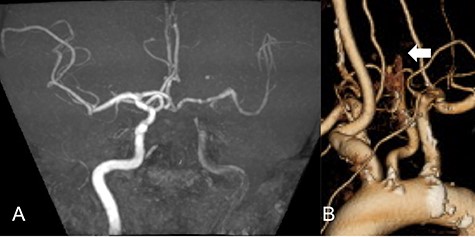

We performed CAS and started dual antiplatelet therapy 27 days after stroke onset to prevent further dissection and cerebral infarction recurrence. The dissection started 1.5-cm below the carotid bifurcation (Fig. 3A). An 8 fr guiding catheter (FlowGate2 Balloon Guide Catheter, Stryker, Fremont, CA, USA) was positioned at the proximal portion of the left CCA with a micro-guidewire (ASAHI CHIKAI Black, Asahi-Intecc, Nagoya, Aichi, Japan) crossing the dissected lesion. A distal protection device (SpiderFx Embolic Protection Device, Medtronic, Minneapolis, MN, USA) was deployed at the petrous portion of the ICA. IVUS was first advanced into the petrous ICA, and vessel wall imaging was performed by slowly withdrawing the device. IVUS imaging confirmed the existence of the dissection’s pseudo-lumen starting 1-cm proximal to the carotid bifurcation (Fig. 3C). IVUS provided the ICA and CCA diameters, which helped decide the most suitable stent (Fig. 3B and C). To adequately cover the dissection lesion, we placed two opened cell stents (Protégé, Medtronic, Minneapolis, MN, USA); one was an 8–6-mm tapered model with a length of 40 mm to cover the lesion from the distal CCA end to the proximal portion of ICA. Another was a 10-mm straight model with a length of 40 mm covering the CCA. Post-dilation was performed SterlingTM Balloon Dilation Catheter (Boston Scientific, Natick, MA, USA) with 5 × 20 mm covering both stents’ edges. The final angiography showed successful treatment with a smooth intra-arterial lumen (Fig. 4A). IVUS imaging showed sufficient stent coverage of the entire dissection lesion. It also confirmed a good expansion of the stent to the dissection area’s arterial wall with no plaque protruding the stents (Fig. 4B).

Angiography revealed the dissection starting proximal to the carotid bifurcation (Black arrow: A). IVUS provided the diameters of the ICA and CCA (B and D, respectively). IVUS imaging confirmed the pseudo-lumen of the dissection starting 1-cm proximal to carotid bifurcation (C) and the entry point of the dissection as well (Black arrow: C).

We would further like to note the usefulness of IVUS in this particular case. IVUS clearly visualized both the dissection’s entry point and the blood flow from true- to pseudo-lumen, the information of which is essential for treatment strategy planning. IVUS also provided helpful information to assess the stent’s coverage (Fig. 3). IVUS allowed us to predict the entire length of the arterial dissection before stent deployment [11]. Furthermore, IVUS provided important information for stent-size selection. Although the pseudo-lumen caused by the dissection made it difficult for us to precisely measure the true lumen diameter, IVUS allowed us to measure the diameter of the true lumen of the dissected artery, and we were able to select the appropriate stent for treatment. It also provided helpful information that proper stent apposition was established even after the stent deployment and post-balloon dilation, which indicated no additional angioplasty was necessary.